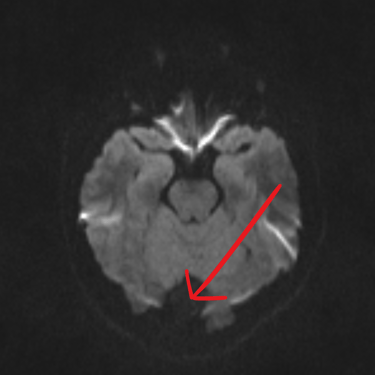

El quiste aracnoideo suboccipital es una lesión benigna de origen congénito, formada por una acumulación de líquido cefalorraquídeo entre las membranas aracnoideas. Aunque en muchos casos puede ser asintomático y detectarse de manera incidental, también puede producir cefalea, mareos, alteraciones del equilibrio o compresión del cerebelo y tronco encefálico. La resonancia magnética (RMN) es el estudio de elección, ya que permite definir la localización, tamaño y sus efectos sobre estructuras adyacentes. Este diagnóstico es clave para establecer la conducta terapéutica, que puede variar entre seguimiento clínico-radiológico o tratamiento quirúrgico en casos sintomáticos o de crecimiento progresivo.